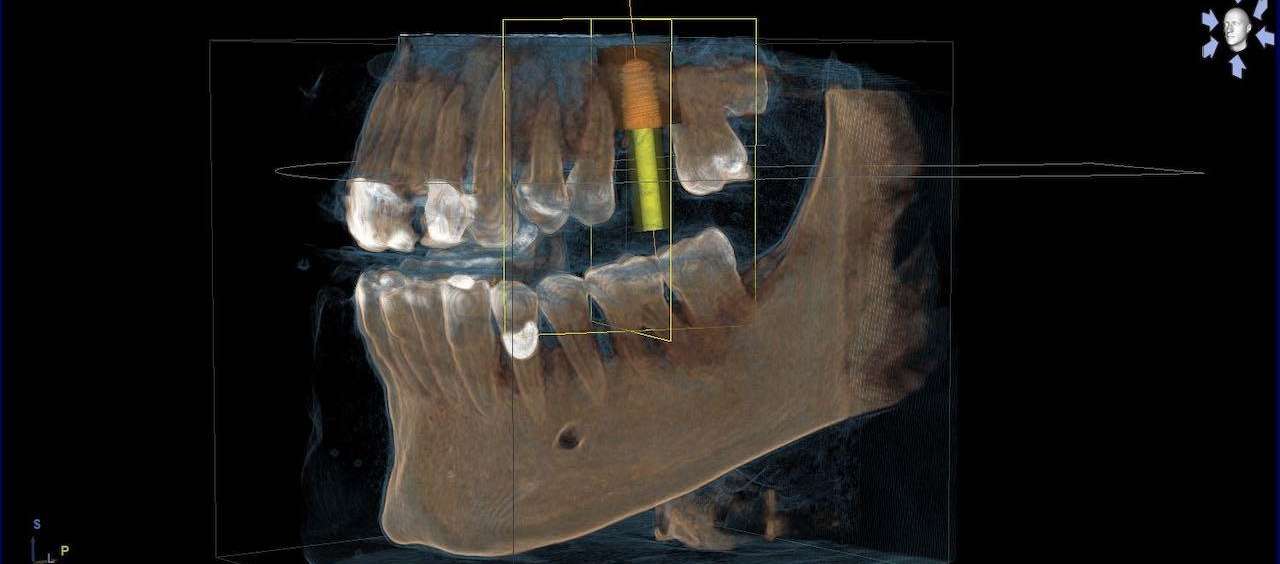

3D x-rays are critically important for diagnostics in dentistry, especially in regards to oral surgery, endodontics (root canal therapy), TMJ/D pathology diagnostics, and implant dentistry. Dr. Nick uses this tech on a daily basis, and many years ago added this very expensive technology to his practice. The CBCT will often catch problems that normal 2-D digital x-rays will not!